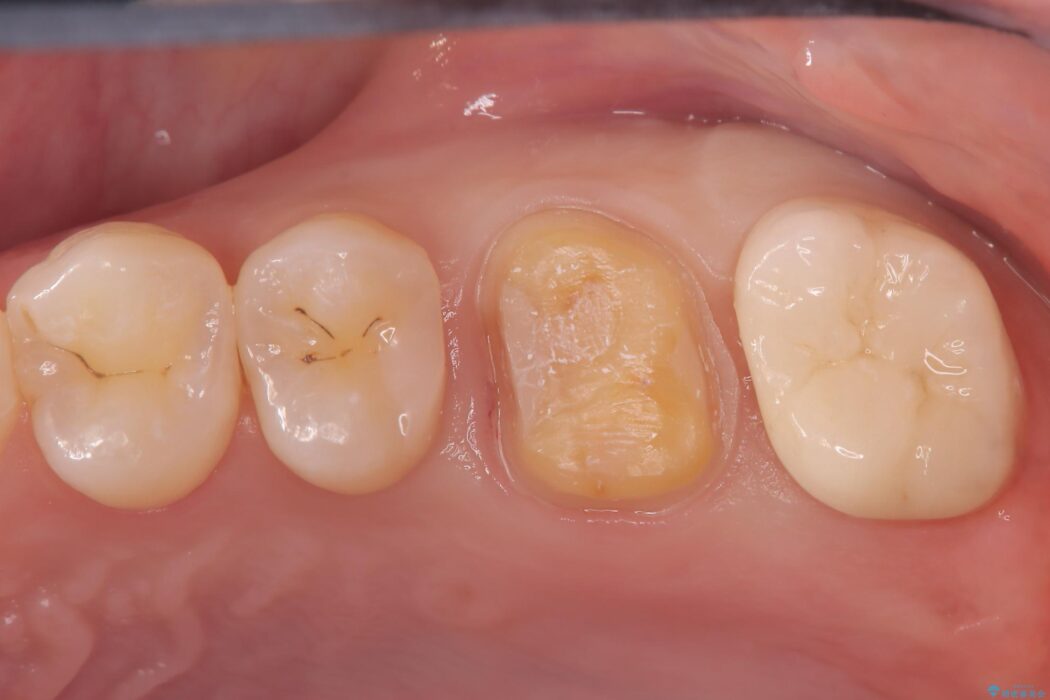

部分的断髄法(MTAの使用): ラバーダム防湿を行い、無菌的な環境下で虫歯を慎重に除去。神経の露出を確認した後、炎症を起こしている一部の神経のみを除去し、残りの健全な神経を保護するためにMTAセメントを充填しました。これにより、神経の機能を維持し、歯を内部から守ることが可能となりました。

経過観察と土台作り: 一定期間の経過を観察し、痛みや炎症がないことを確認。神経の生存を確認した上で、セラミックを支えるための土台を精密に構築しました。